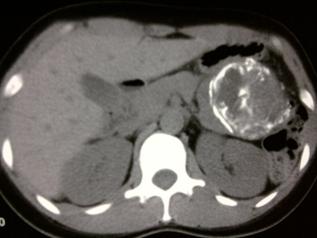

Calcified Metastases From Malignant Ovarian Neoplasm

With metastatic lymph node calcifications and calcified metastasis to the breast. This will be first case to appear in the literature. We shall also present the fourth reported case of calcifica- Vol. 113 CALCIFIED METASTASES FROM MALIGNANT OVARIAN NEOPLASM ... Retrieve Document